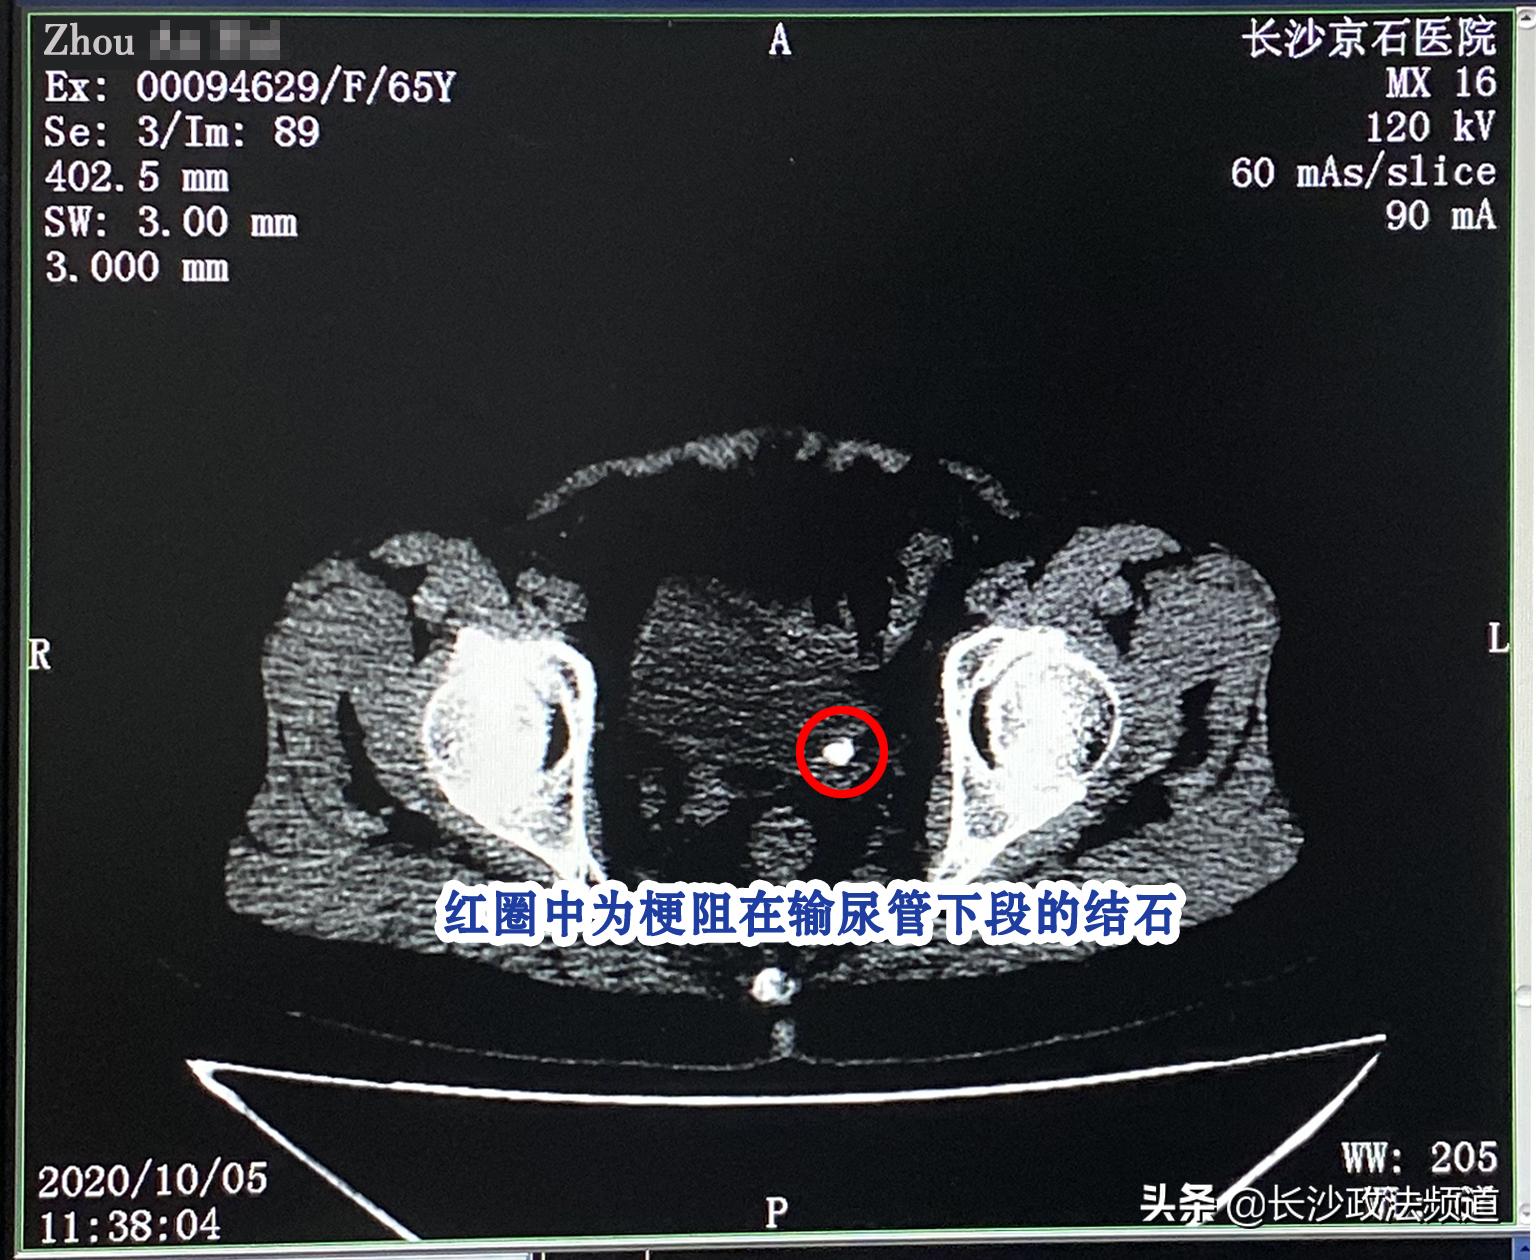

直到9月份周女士决心找出感染“源头”,第三次入院进行了全方位的详细体检,经彩超检查才揪出了真凶!原来竟是一枚梗阻在输尿管下段的结石,导致肾脏积水,才一直炎症不退。

周女士CT检查局部图